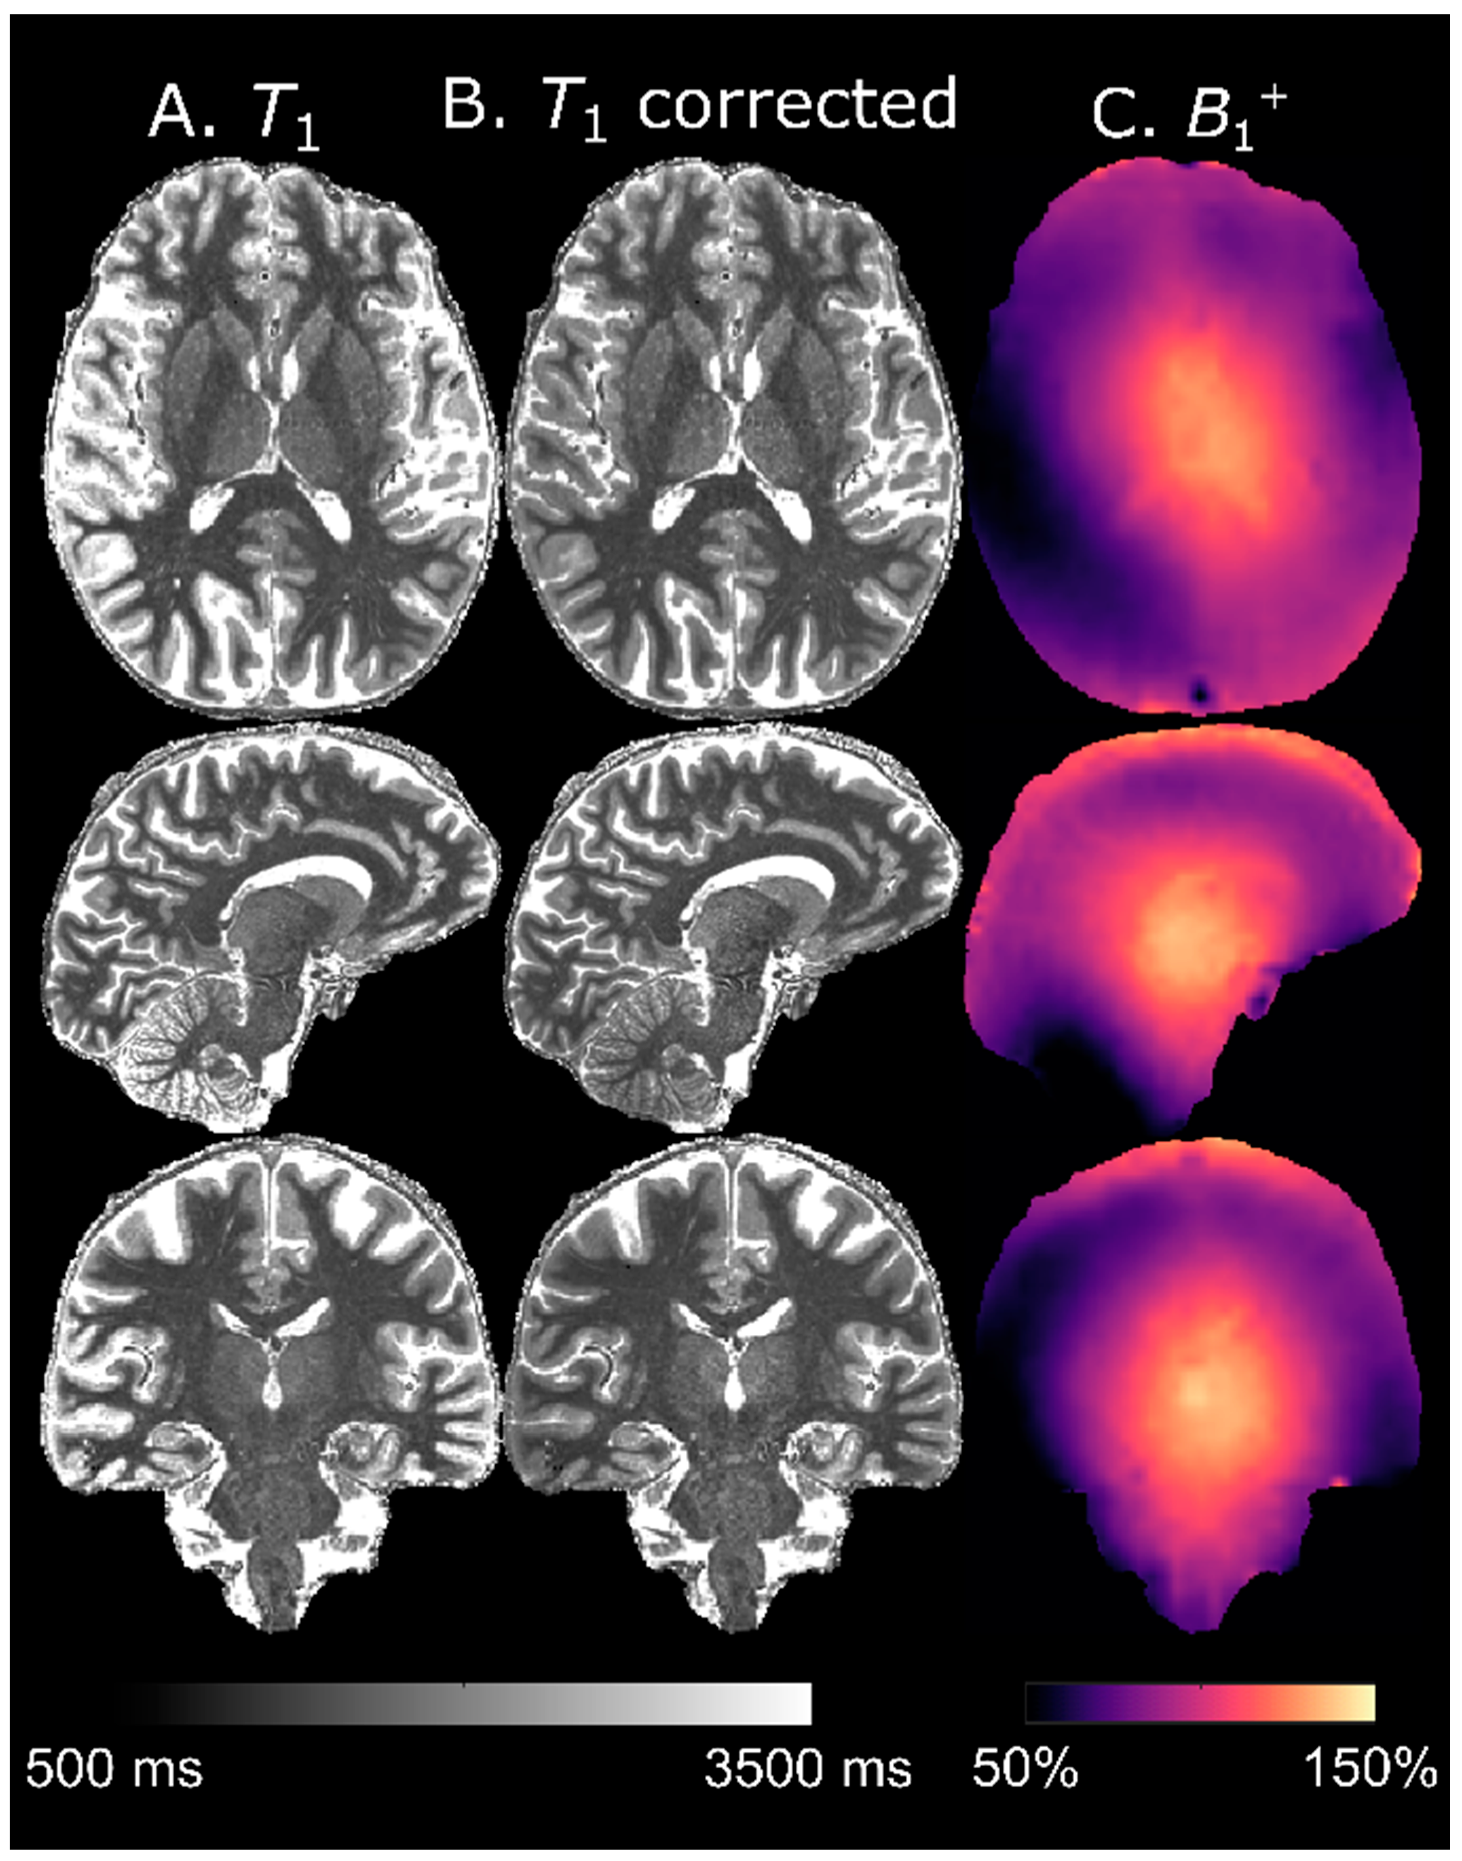

3.7. T1 Calculation

The evolution of M ˜ z , MP over Tcycle for TF = 288 is shown in panel A of Figure 7. The LUT signals were derived from this evolution for different T1s and fT = 1 (panel B). The resulting T1 as a function of SMP2RAGE at different fT values is also shown (panel C). For these sequence parameters, the B1+ bias was most pronounced at long T1 (i.e., for CSF). Around approximately 1000 ms, however, T1 was no longer uniquely defined for a given SMP2RAGE, which thus set the lower limit of measurable T1. This lower limit varied, based on fT as 1122/1156/1181/1169/1097/966/810 ms for fT = 0.4/0.6/0.8/1.0/1.2/1.4/1.6, respectively. At fT = 0.4, there was also an upper limit at 3330 ms. Figure 8 shows a map of T1 derived from this LUT before (panel A) and after (panel B) B1+-correction. Estimated tissue T1 was only moderately affected by the B1+-correction although an elevation of T1 in the thalamus (fT ≈ 1.3) after correction can be discerned. The most notable difference was seen in the CSF, which was adjusted toward higher values in high B1+ areas and toward lower values in low B1+ areas. Especially after correction, the distribution of T1 seemed to be very homogenous within different tissues, without any obvious B1+ bias.

Figure 8. LUT-derived T1 maps, uncorrected (A) and corrected (B) with a separately acquired B1+ map (C). The T1 estimation in tissue was moderately robust against B1+ influence and mostly CSF was affected.